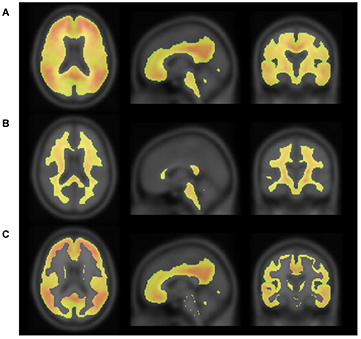

Figure 2 shows the process of making an empirically PiB-prone ROI template (EPP-ROI). Voxels, in which PiB accumulation was higher than 1.7 in SUVR, were extracted from the positive template. Non-specific PiB accumulative voxels, which actually covers the white matter, were also extracted from the negative template based on the SUVR cutoff value of 1.7. We adopted the SUVR cutoff value of 1.7 to make non-specific PiB accumulations of the negative template fit the white matter of average MRI (figure 3) by discussions among nuclear medicine physicians and technologists. We then generated the EPP-ROI by subtracting the negative mask from the positive mask and further selecting voxels overlapping with one of the following AAL-ROIs (Tzourio-Mazoyer et al 2002) that were considered important: 'Precentral' (precentral gyrus), 'Rolandic_Oper' (rolandic operculum), 'Supp_Motor_Area' (supplementary motor area), 'Frontal_Sup' (superior frontal gyrus), 'Frontal_Mid' (middle frontal gyrus), 'Frontal_Inf' (inferior frontal gyrus), 'Rectus' (rectus gyrus), 'Cingulum_Ant' (anterior cingulate gyrus), 'Cingulum_Mid' (middle cingulate gyrus), 'Postcentral' (postcentral gyrus), 'SupraMarginal' (supramarginal gyrus), 'Angular' (angular gyrus), 'Parietal' (superior and inferior parietal gyrus), 'Cingulum_Post' (posterior cingulate gyrus), 'Precuneus' (precuneus), 'Calcarine' (calcarine fissure and surrounding cortex), 'Cuneus' (cuneus), 'Occipital' (occipital gyrus), 'Fusiform' (fusiform gyrus), 'Temporal' (superior, middle and inferior temporal gyrus), 'Putamen' (putamen) and 'Pallidum' (globus pallidus) (figure 4).

Figure 2. Positive (A) and negative (B) masks, consisting of voxels with SUVR of more than 1.7. PiB-prone areas were generated by subtracting the negative mask from the positive mask (C).